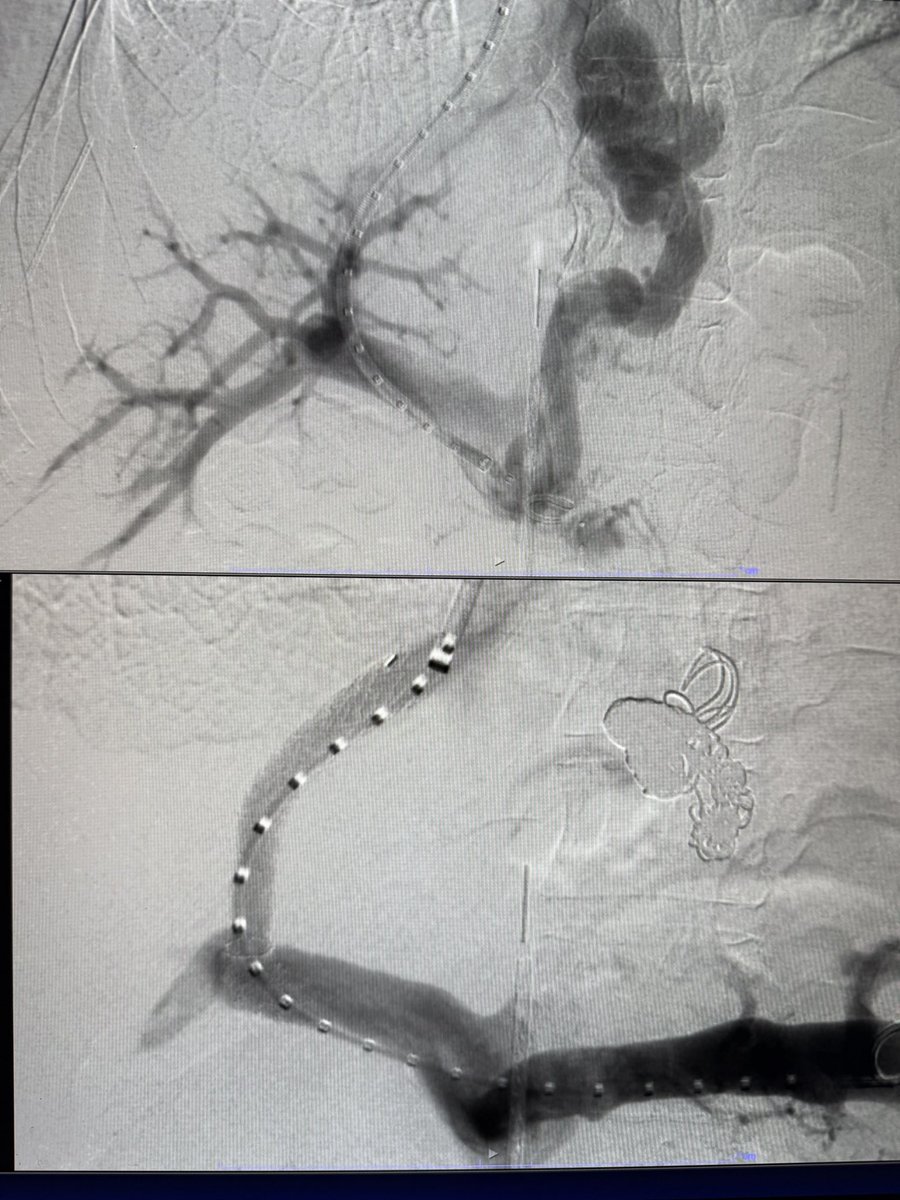

Life saving intervention..looking back 25 some years, couldn’t know in my wildest dreams that I would be able to, but I am fortunate & it has been a privilege to be able to offer it to patients in dire circumstances.

4 TIPS this week, 3/4 with moderate sedation, all under 30 mins to stent deployment. ICE and steerable needles are the future!